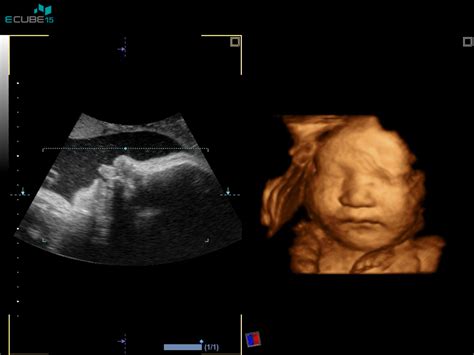

Tehnično gledano, 3D/4D ultrazvok temelji na nizu zaporednih 2D slik, ki se sestavijo v tridimenzionalno ali štiridimenzionalno (časovno dimenzijo) podobo. 3D ultrazvok omogoča boljše merjenje in preverjanje volumnov ter prikazuje tridimenzionalne slike telesnih značilnosti, organov ali delov telesa. Najpogosteje se 3D/4D UZ uporablja za prikazovanje določenih delov plodovega telesa staršem, da si ga lahko bolje predstavljajo, kot pa za pridobivanje dodatnih diagnostičnih informacij. Učinkovitost te tehnologije je odvisna od usposobljenosti ginekologa.